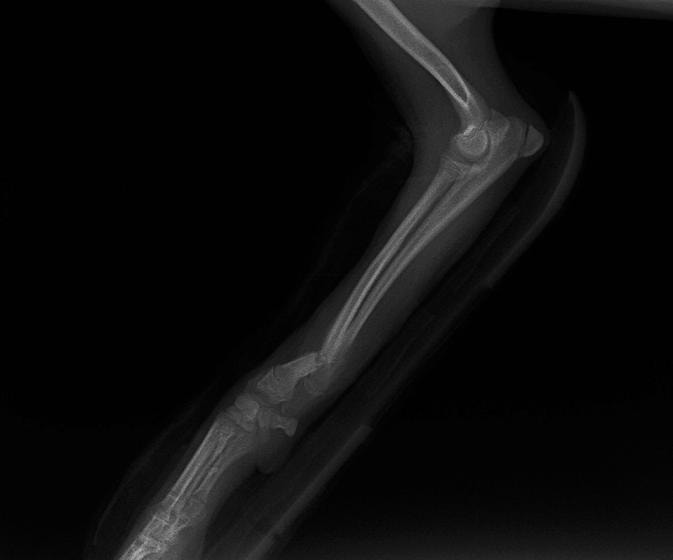

ペルシャ猫 11ヶ月齢 雄

他院にて左大腿骨遠位の成長板骨折(salter-harrisⅠ型)が認められており、治療相談を目的として来院。当院にて、キルシュナーワイヤーを用いたピンニングにより骨折部位の整復を行いました。術後の経過は良好で、現在も経過観察中です。

術前レントゲン

術後レントゲン